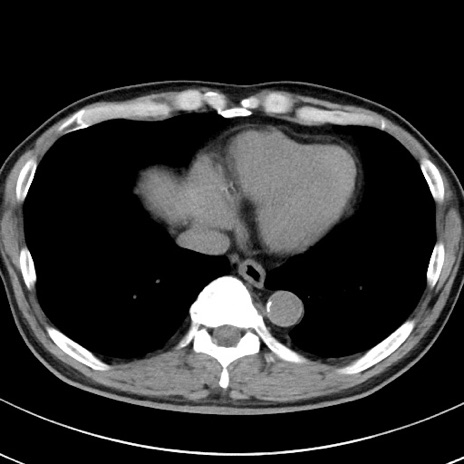

【腹部TIPS】症例29 参考症例 CT(横断像)

症例

70歳代男性